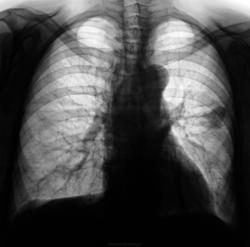

Пациентка, при расшифровке флюорограмм, была взята на контроль. Произведена рентгенография в стандартных проекциях. Ваше мнение уважаемые коллеги?

Дифференцируем туберкулому и ретенционную кисту....

После коррекции Виктора Владимировича еще больше склоняюсь к ретенционной кисте....

Ретенционная киста....

Что касается выводов, то теперь вернулся к самому первому своему выводу : туберкулома?-ретенционная киста?

Пациентка в течение 12 лет состоит на учете в туб. кабинете по поводу туберкуломы, Пациентке неоднократно предлагалась операция, от которой она упорно отказывалась и отказывается по каким - то своим соображениям. В прошлом году было и СКТ и бронхоскопия и ЦВК, вся необходимая атрибутика выдержана. Случай верифицирован. Время от времени пациентку направляют в рентгеновский кабинет для наблюдения "динамики".